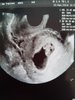

Jest ciąża[emoji3]ale moim zdaniem za wcześnie w poniedziałek ja tak pognałam przy becie 500i nic nie było widać i już schiza że ciąża pozamaciczna[emoji3]hej dziewczyny zrobiłam bete wyszla 59 co o tym myslicie ??? w poniedziałek do gina ide zobaczymy co powie trzymajcie kciuki